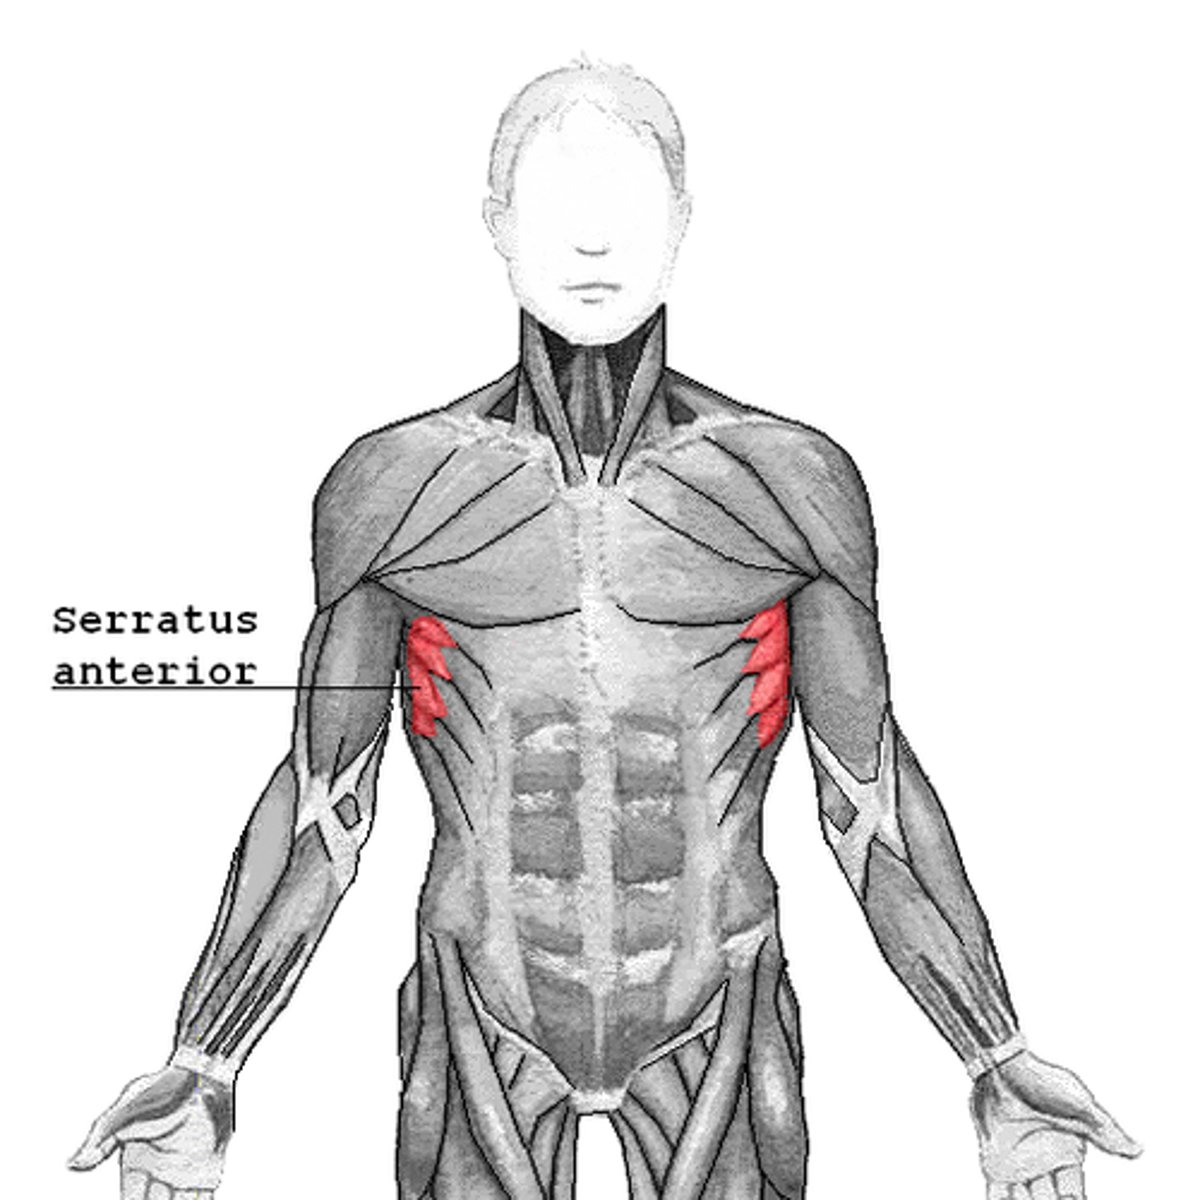

(Anterior axioappendicular muscles:) Serratus anterior

-Protracts and stabilizes scapula

-Long thoracic n. (C5 - C7)